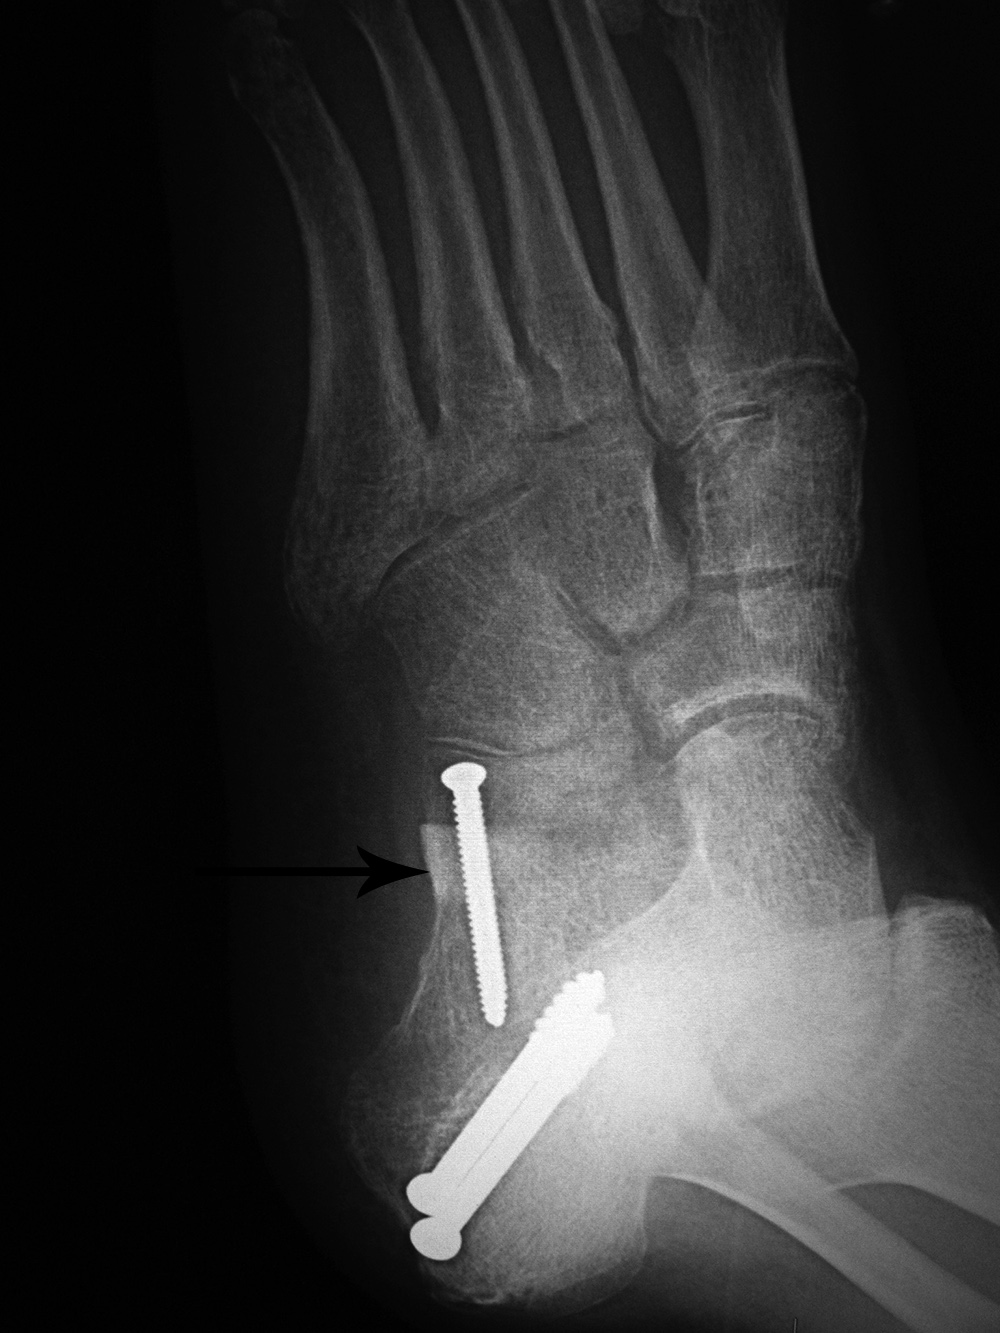

46 year-old man with posterior tibial tendon tear, Achilles tendon contracture, and planovalgus foot alignment. He was treated with Achilles tendon reattachment and two large partially threaded cancellous bone screws stabilizing a mid-calcaneal osteotomy. In the anterior portion of the calcaneus there is an autogenous iliac crest bone plug (arrow) stabilized by a fully threaded cortical bone screw.